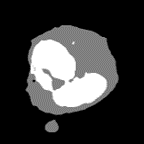

4.2.1 White Blood Cell

White Blood Cell(WBC) [45] consists of 100 images of 300×300300300300\times 300 pixels in three classes: cell nucleus of white blood cells, cytoplasm, and background including red blood cells. For the experiment, the images were resized to 320×320320320320\times 320 pixels by bilinear interpolation. 64 images were training images, 16 images were validation images, and 20 images were test images. The batch size is set to 2 for training. In the segmentation images, white color indicates cell nucleus, gray color indicates cytoplasm, and black color indicates the background including red blood cells.

Figure 5: Segmentation result on WBC dataset

4.3.1 Results on WBC dataset

We use U-Net [28] as a baseline, which has been widely applied in medical and biological images. Following methods are the comparison methods. two adversarial training methods; pix2pix [15] based on U-Net with a discriminator and Self-Attention GAN (SAGAN) [43] which adds Self-Attention [36] to the discriminator of pix2pix. We also evaluate attention U-Net [23] introduced an attention mechanism called sSE-Block [29] to Skip Connection of U-Net. PDA-Module [21] is a method that applies a bottom-up attention mechanism based on difficulty to U-Net.

Table 2 shows the IoU accuracy on the WBC dataset, and Table 2 shows the experimental results of evaluating WBC dataset with Precision and Recall. Bold red letters in Table represent the best accuracy, and blue and green bold letters are the second and third best. We see that the accuracy of AML-Net is better than that of conventional methods based on U-Net. In particular, we confirm that the accuracies of Top-Down PDA-Module and AML-Net were improved in almost classes compared to pix2pix and SAGAN, which are adversarial training methods without leakage. Especially, in cytoplasm which is the most difficult, large accuracy improvement was observed. In addition, the accuracy of AML-Net was better than other conventional methods in terms of the mean and standard deviation. This indicates that the accuracy of AML-Net is stable and does not depend on the combination of datasets or initial values. In addition, we confirm that the mean IoU of AML-Net based on U-Net is higher than that of Deeplabv3+ [3] and FastFCN [40] based on ResNet-50 [8]. By avoiding the use of very deep networks such as ResNet-50, the training and inference speed can be accelerated, which is an advantage for cell biologists in practical use. From Table 2, we can see that AML-Net has the best Recall for cytoplasm and cell nucleus, and Precision also shows high accuracy. Conventional methods only have high precision or high recall, but AML-Net has an advantage in the balance of precision and recall.

Figure 5 shows segmentation results. We see that the most of conventional methods in the upper image group over-detect the cytoplasm because the color of red blood cells and cytoplasm are similar. In addition, in the lower image group, we can see that the cytoplasm staining is darker and therefore closer to the color of the cell nucleus, and that segmentation is not working well with many conventional methods. Our AML-Net can accurately segment the regions even for images with very similar colors.